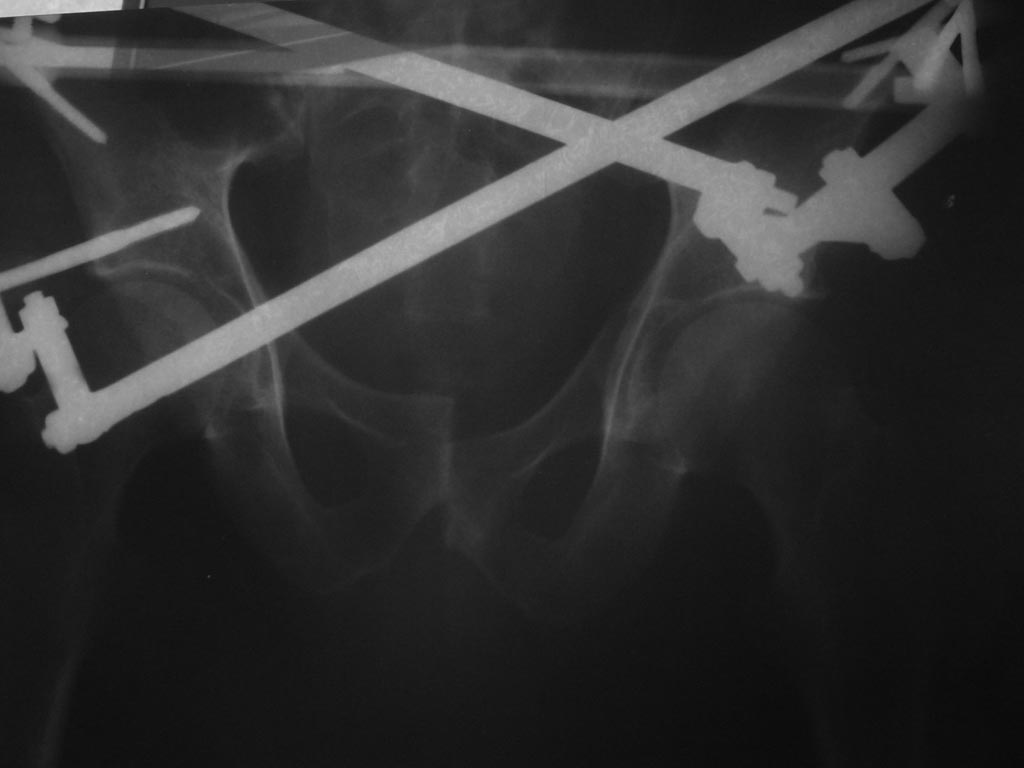

Я клинический ординатор по специальности травматолог-ортопед в НЦ РВХ города Иркутска. Ко мне обратился знакомый из бурятии. в начале июля этого года в результате ДТП получил травму таза (разрыв лонного сочленения и разрав кресцово подвздошного сочленения справа.Дислокация правой половины теза кверху.Вертикально нестабильное повреждение таза типа С

Про месту травмы лечился на скелетном вытяжении, репозиция не достигнута. В конце июля прооперирован по месту жительства: закрытая репозиция таза, фиксация в АВФ. Репозиция не достигнута. Выисан на амбулаторное лечение. В данный момент беспокоят постоянные боли, деформация, невозможность пользоваться правой нижней конечность, и в связи со всем перечисленным проблемы с активизацией. Консультировался со старшими коллегами по поводу возможности лечения в нашей клинике. На что получил ответ что "недостаточно опыта в лечении подобных травм и их последствий". Прошу помочь в решении данного вопроса. С уважением Чингиз Бутаев.